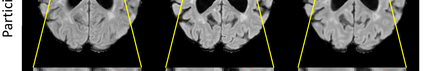

Multiple Sclerosis (MS) is a chronic progressive neurological disease characterized by the development of lesions in the white matter of the brain. T2-fluid-attenuated inversion recovery (FLAIR) brain magnetic resonance imaging (MRI) provides superior visualization and characterization of MS lesions, relative to other MRI modalities. Longitudinal brain FLAIR MRI in MS, involving repetitively imaging a patient over time, provides helpful information for clinicians towards monitoring disease progression. Predicting future whole brain MRI examinations with variable time lag has only been attempted in limited applications, such as healthy aging and structural degeneration in Alzheimer's Disease. In this article, we present novel modifications to deep learning architectures for MS FLAIR image synthesis, in order to support prediction of longitudinal images in a flexible continuous way. This is achieved with learned transposed convolutions, which support modelling time as a spatially distributed array with variable temporal properties at different spatial locations. Thus, this approach can theoretically model spatially-specific time-dependent brain development, supporting the modelling of more rapid growth at appropriate physical locations, such as the site of an MS brain lesion. This approach also supports the clinician user to define how far into the future a predicted examination should target. Accurate prediction of future rounds of imaging can inform clinicians of potentially poor patient outcomes, which may be able to contribute to earlier treatment and better prognoses. Four distinct deep learning architectures have been developed. The ISBI2015 longitudinal MS dataset was used to validate and compare our proposed approaches. Results demonstrate that a modified ACGAN achieves the best performance and reduces variability in model accuracy.